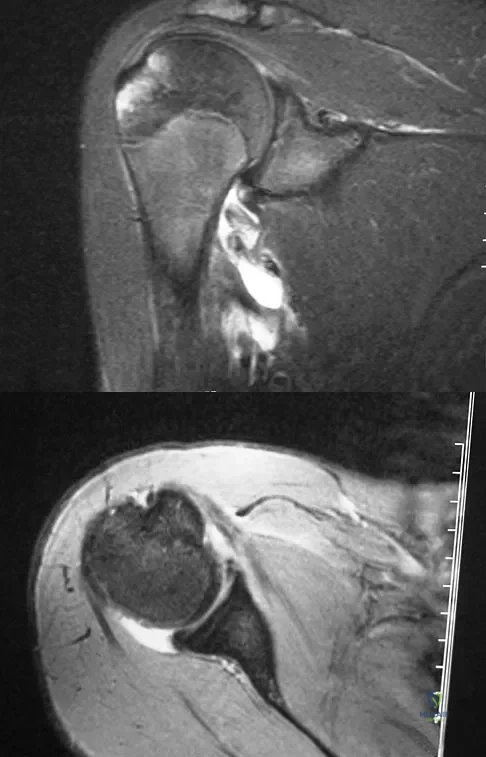

A 15-year-old wrestler sustains an abduction, hyperextension, and external rotation injury to his right shoulder. The MRI scan findings shown in Figures 27a and 27b are most consistent with

Explanation